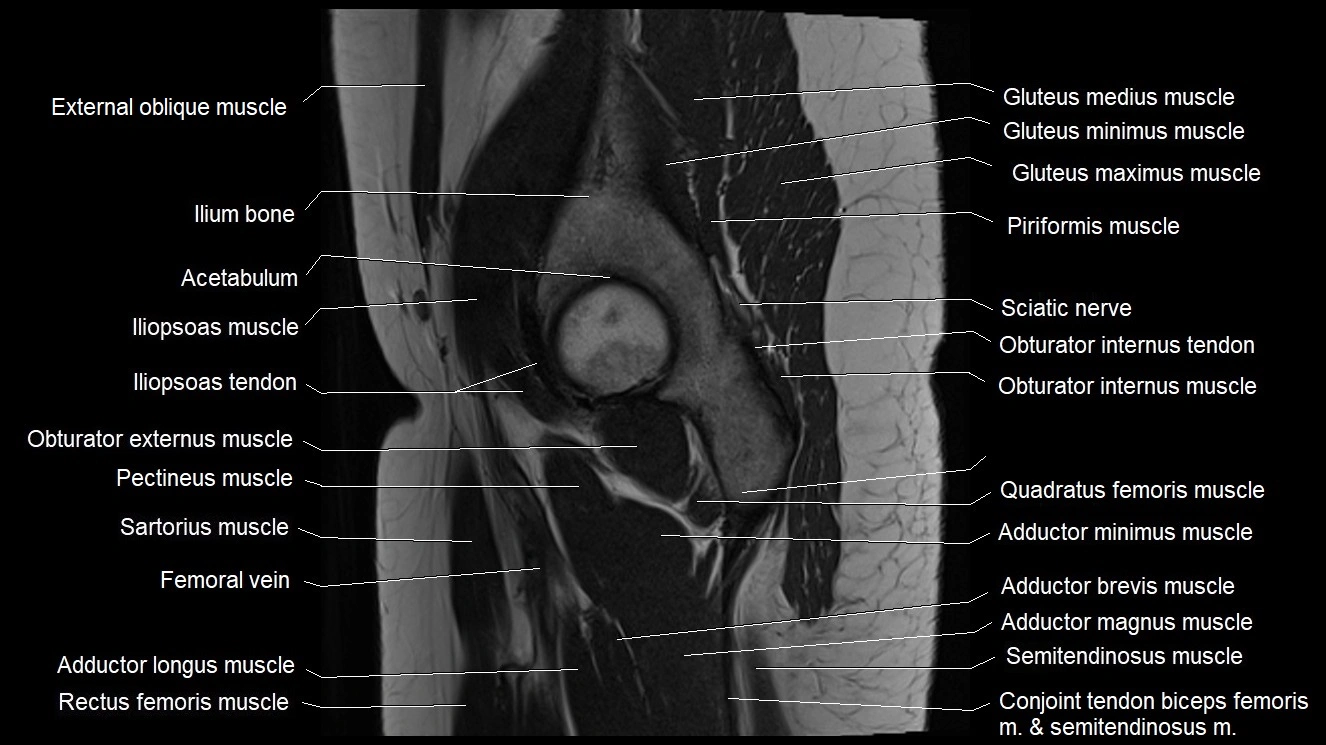

- Acetabulum

- Adductor brevis muscle

- Adductor longus muscle

- Adductor magnus muscle

- Adductor minimus muscle

- Conjoint tendon of biceps femoris & semitendinosus

- Femoral vein

- Gluteus maximus muscle

- Gluteus medius muscle

- Gluteus minimus muscle

- Gracilis muscle

- Iliopsoas muscle

- Iliopsoas tendon

- Ilium bone

- Inferior gemellus muscle

- Obturator externus muscle

- Obturator internus muscle

- Obturator internus tendon

- Pectineus muscle

- Quadratus femoris muscle

- Sartorius muscle

- Superior gemellus muscle